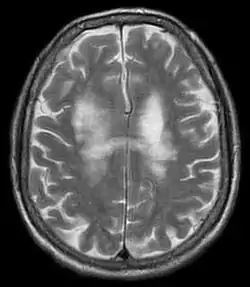

![]() تصوير بالرنين المغناطيسي يوضح الإصابة باعتلال بيضاء الدماغ متعدد البؤر المترقي تصوير بالرنين المغناطيسي يوضح الإصابة باعتلال بيضاء الدماغ متعدد البؤر المترقي | |